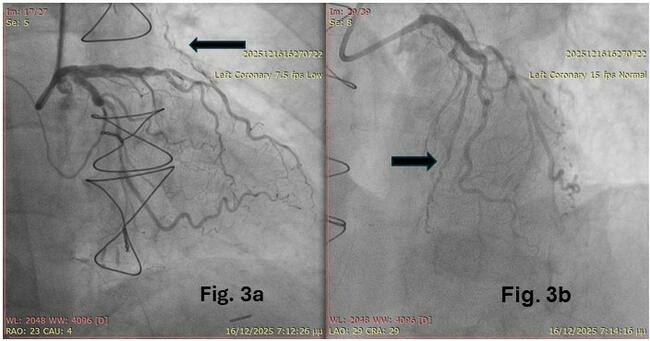

A Challenging Case of Left Main Chronic Total Occlusion and the Reverse T-Stenting and Small Protrusion (TAP) Technique: Success With the Investment Strategy

Video Supplement to "A Challenging Case of Left Main Chronic Total Occlusion and the Reverse T-Stenting and Small Protrusion (TAP) Technique: Success With the Investment Strategy" (Clinical Image).